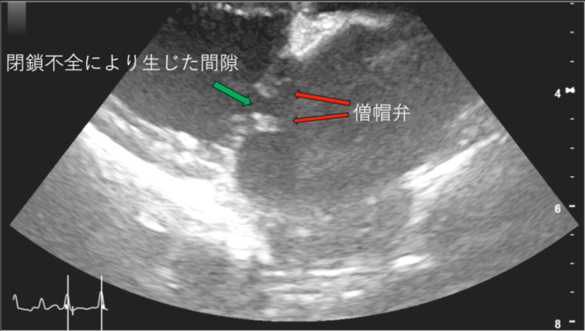

わんちゃんで発生の多い心臓病は、「僧帽弁閉鎖不全症」です。

「僧帽弁」とは、「左心房と左心室」を隔てている弁であり、

「僧帽弁閉鎖不全症」とは、この「僧帽弁」がきちんと閉まらなくなる病気です。

本来、左心房から左心室へ一方向に血液が流れますが、

僧帽弁が完全に閉まらないため、左心室から左心房へ血液が逆流します。